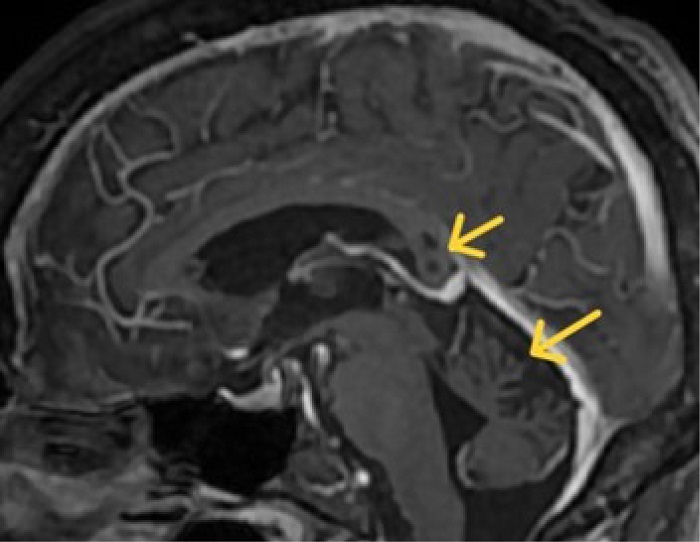

Brain magnetic resonance imaging (MRI) reveals global atrophy, predominantly affecting the cerebellar vermis, with three lesions exhibiting hypointensity on T1 and hyperintensity on T2 in the splenium of the corpus callosum ( Figures 1 and 2). No restriction in water diffusion or enhance with gadolinium was noted.

The typical presentation involves lesions with a cystic appearance or an edema/demyelinating substrate, generally located in the corpus callosum, which may also affect the deep white matter. The number and characteristics of the lesions may change with disease progression. Fewer lesions, restricted diffusion, and gadolinium enhancement typically indicate an acute process 2, 4, 5.